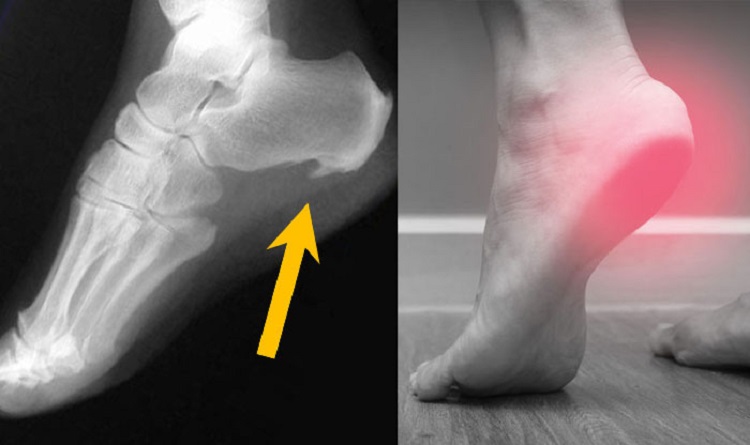

اگر فردی این علائم را داشته باشد، پزشک برای تشخیص مشکل او از اشعه‌ی ایکس استفاده می‌کند. مشاهده‌ی برآمدگی با استفاده از اشعه‌ی ایکس، تنها راه اطمینان یافتن از وجود مشکل خار پاشنه در فرد است. البته تمام علائم بالا در همه‌ی افرادی که دچار خار پاشنه هستند، مشاهده نمی‌شود. بعضی از افراد مبتلا به خار پاشنه هیچ علامتی ندارند. این افراد تنها زمانی متوجه خار پاشنه‌ی خود می‌شوند که پای آن‌ها به‌دلیل مشکل دیگری توسط اشعه‌ی ایکس بررسی شود.

خار پاشنه پا را چگونه می‌توان تشخیص داد؟

بهترین راه برای تشخیص درست عارضه خار پاشنه پا، مراجعه به پزشک است. پزشک نیز از طریق راه‌های مختلفی بررسی سوابق پزشکی بیمار و معاینه فیزیکی قادر به تشخیص این عارضه است، اما در هر صورت متداول‌ترین راه تشخیص خار پاشنه پا، معینه است. شیوه‌های تشخیص عارضه خار پاشنه پا را می‌توان به روش‌های متداول ذیل تقسیم کرد؛

۱. بررسی سوابق بیمار: خار پاشنه یا کالکانئال که در عکس‌های گرفته شده به وسیله اشعه ایکس قابل مشاهده است. معمولاً بدون علامت و نشانه هستند. افرادی که دچار درد در پاشنه پا هستند علائمی را در هنگام انجام فعالیت‌هایی که باعث فشار وزن بدن بر روی پا‌ها می‌شود مانند ایستادن و راه رفتن و همچنین در هنگام استفاده از کفش‌های نامناسب یا کفش‌های با کفی ناکافی گزارش داده‌اند.

۲. انجام معاینات فیزیکی: بسیاری از خار‌های پاشنه در معاینات مشخص نمی‌شود، اما وقتی که پزشک پاشنه پا را لمس می‌کند ممکن است افرادی که دارای خار پاشنه پا هستند احساس درد و ناراحتی کنند. در افرادی که خار پاشنه دارند ممکن است محل اتصال تاندون آشیل به استخوان پاشنه به لمس حساس باشد.

۳. انجام آزمایشات متناسب: بسیاری از خار‌های پاشنه پا معمولاً به صورت اتفاقی در عکس‌های گرفته شده با اشعه ایکس که به دلایل دیگری گرفته شده‌اند، دیده می‌شوند. اکثر افرادی که خار پاشنه پای آن‌ها در عکس‌های گرفته شده به وسیله اشعه ایکس دیده شده، هیچ علائمی نداشته‌اند. اگر علائم درد پاشنه پا باعث اختلال ماهیچه‌ای یا عصبی شود باید آزمایش‌های دیگری مثل ام آر آی، سی تی اسکن یا الکترومیوگرافی انجام شود.